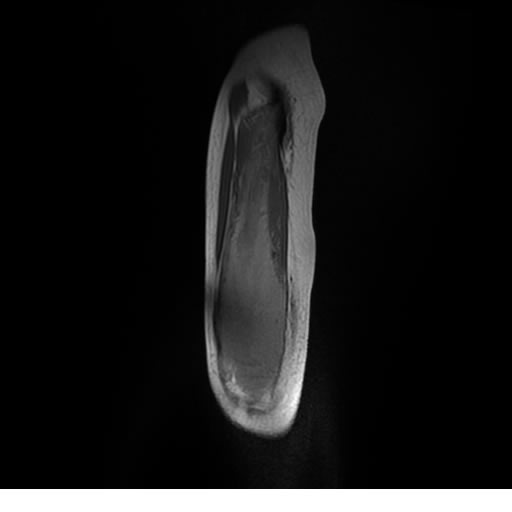

Se realiza estudio de MRI de muslo izquierdo en diferentes planos, con secuencias de Spin Echo, GRE; ponderadas a T1 y a T2, se utilizan pulsos de saturación de grasa y se administra medio de contraste IV a base de Gadolinio en base al peso del paciente.

La diáfisis femoral izquierda muestra reacción perióstica importante, se extiende desde el cuello del fémur, invade trocánteres, diáfisis femoral, medial y distal, es compatible con un proceso infeccioso óseo, el complejo muscular del muslo se ve edematizado.

Hallazgos en Resonancia Magnética (RM)

La resonancia es la modalidad de elección para valorar la extensión intramedular y la infiltración en tejidos blandos, brindando una imagen más detallada del compromiso tumoral. Los hallazgos característicos incluyen:

Lesión de señal heterogénea en secuencias T1 (hipointensa) y T2/STIR (hiperintensa), que refleja necrosis, hemorragia y contenido celular diverso.

Realce intenso y heterogéneo tras la administración de contraste (gadolino), lo que indica vascularización tumoral.

Compromiso de la médula ósea adyacente y de estructuras vecinas, como músculos y neurovasculatura.

Posible presencia de edema óseo y necrosis central.